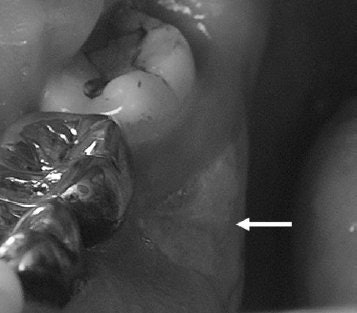

![]() |

| A 61-year-old man with metastatic prostate cancer treated with zoledronate presents with painful bone exposure of the right mandible (arrow). Phal PM, Myall RWT, Assael LA, Weissman JL, "Imaging Findings of Bisphosphonate-Associated Osteonecrosis of the Jaws," American Journal of Neuroradiology, Vol. 28:6, pp 1139-1145. © American Society of Neuroradiology. |

In this retrospective study, Dr. Phal's group included 15 patients on bisphosphonates who developed osteonecrosis of the jaws. Among the 11 female subjects, six had breast cancer, three had osteoporosis, and two had multiple myeloma. Among the four male patients, there were two cases of prostate cancer, one of multiple myeloma, and one of osteoporosis.